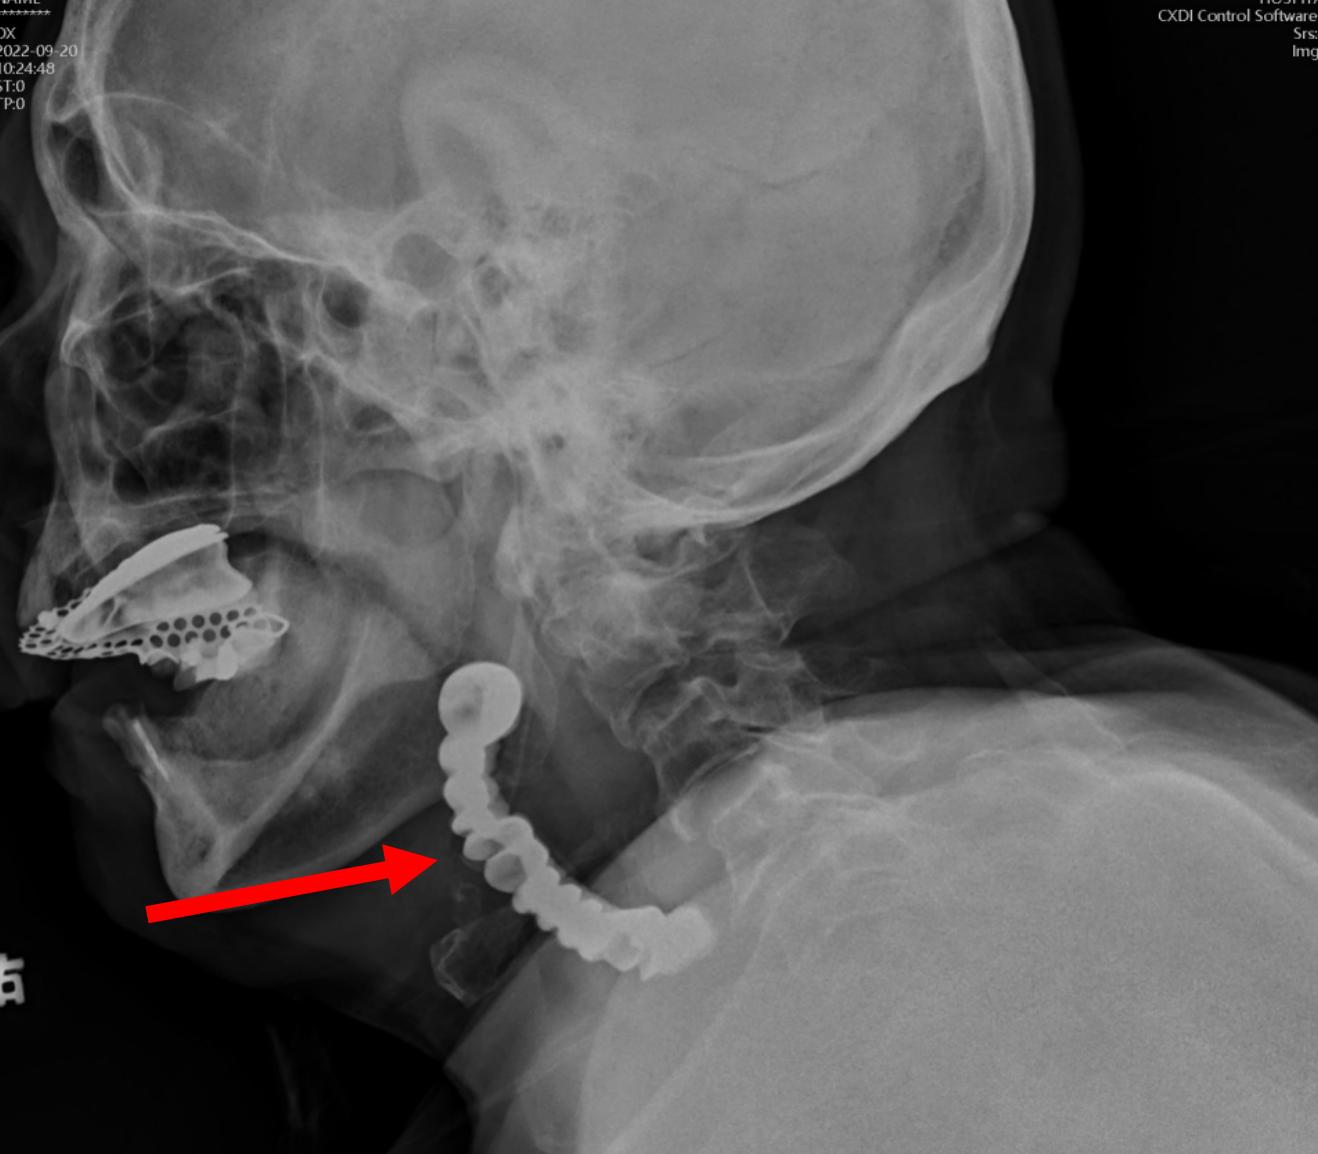

假牙异物位于人体的“交通要道”——会厌谷及食道入口

广东省第二人民医院耳鼻咽喉头颈外科主任医师傅向军为林大爷做了影像检查,结果显示为“下咽食道入口异物”。同时,林大爷基础疾病较多,曾做过心脏起搏器置入和冠心病支架置入手术,最近又因为摔倒导致耻骨骨折,身体十分虚弱。对于高龄合并多种疾病的情况,手术的风险较高。

而当手术团队正准备气管插管,以保证术中供氧的时候,又遇到一道难题:假牙卡在会厌谷与梨状窝,也就是气道与食道的“十字路口”,难以抬起会厌,气管插管困难。

傅向军主任医师借助可视喉镜巧妙取异物

如果不能气管插管,就不能使用食管镜,意味着无法取出异物。这时,傅向军主任医师建议,采用弯曲可视喉镜,终于看见了目标物——假牙。但是假牙位置较深,普通的器械主体多为直线,不符合舌根后的弧线结构,难以将其取出。傅向军主任医师改为使用卵圆钳,慢慢一点点往外移动,终于将“罪魁祸首”一整排假牙取出。幸好,此假牙为下颌义齿,无金属挂钩,没有明显将林大爷口腔和咽喉的黏膜切割伤。